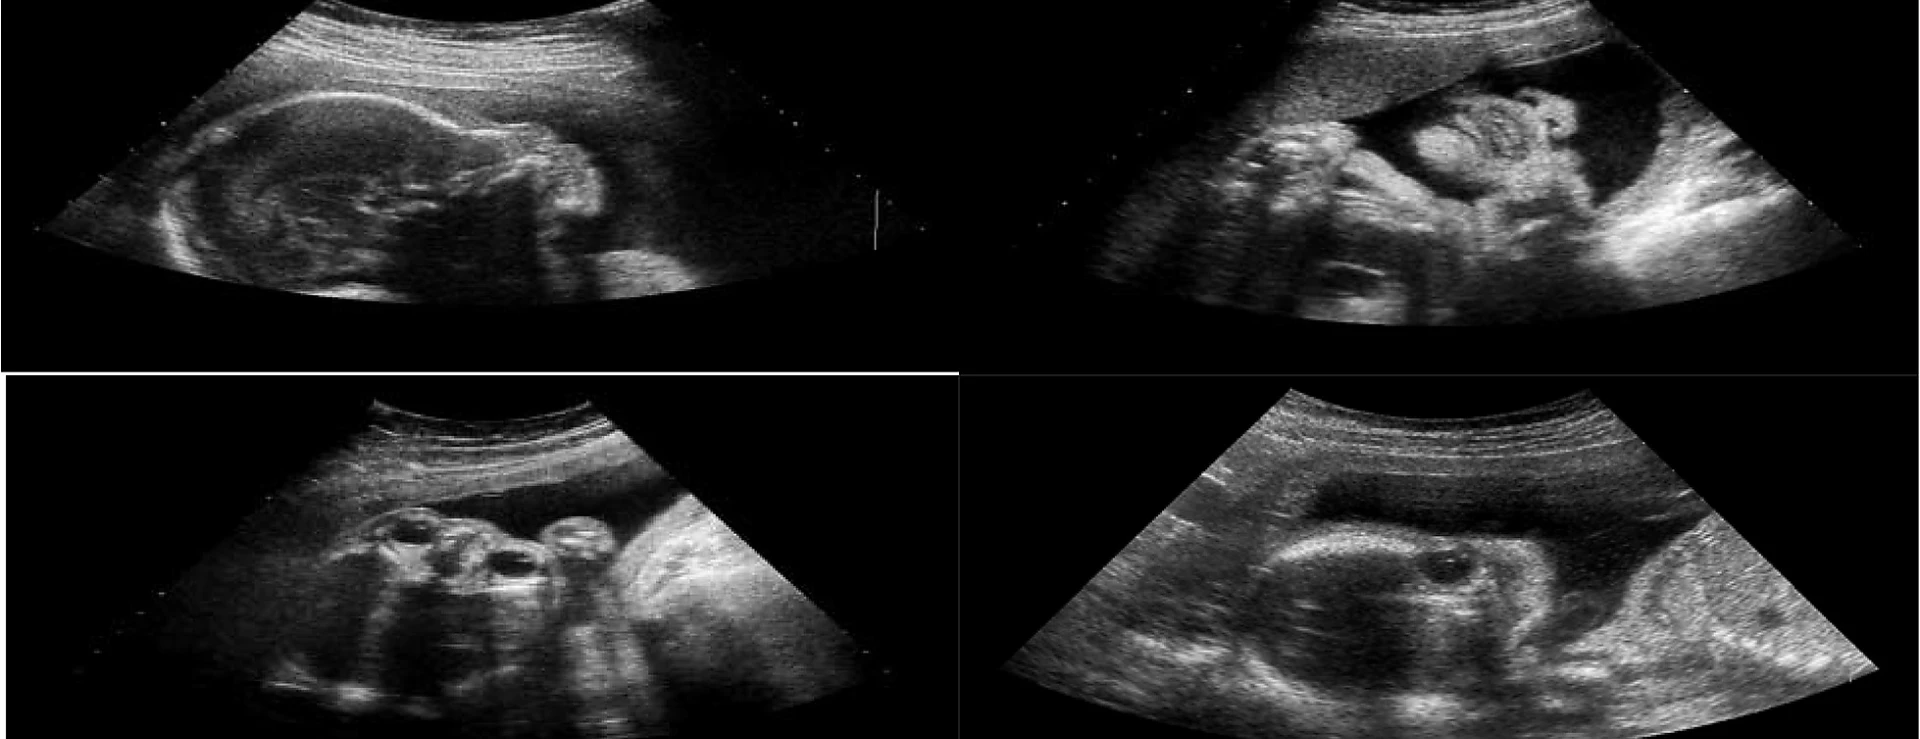

Quá trình thực hiện siêu âm hình thái thai nhi diễn ra trong một môi trường y tế chuyên nghiệp và an toàn, đảm bảo thu thập các thông tin cần thiết để đánh giá sức khỏe và sự phát triển của thai nhi. Đầu tiên, mẹ bầu sẽ được hướng dẫn nằm trên bàn khám, nơi bác sĩ sẽ bôi gel siêu âm lên vùng bụng. Gel này có tác dụng tăng cường độ dẫn truyền sóng âm, từ đó tạo ra hình ảnh rõ nét về các cơ quan bên trong.

Tiếp theo, bác sĩ sẽ sử dụng đầu dò siêu âm di chuyển trên vùng bụng để thu thập hình ảnh. Quá trình này thường kéo dài từ 15 đến 30 phút tùy thuộc vào việc thu thập hình ảnh cụ thể. Trong thời gian này, mẹ bầu có thể tham gia quan sát trực tiếp các hình ảnh của em bé được hiển thị trên màn hình, một trải nghiệm xúc động đối với nhiều người.

Các chỉ số quan trọng như nhịp tim, kích thước đầu, chiều dài xương và kích thước bụng của thai nhi sẽ được đo và ghi lại trong quá trình siêu âm. Những dữ liệu này sẽ giúp bác sĩ đưa ra các đánh giá tổng quan về sức khỏe và sự phát triển của thai nhi. Nếu phát hiện những bất thường, bác sĩ có thể đề xuất thêm các xét nghiệm hoặc phương pháp kiểm tra chuyên sâu khác để xác định rõ ràng các vấn đề.

Quá trình kết thúc khi tất cả các chỉ số cần thiết đã được ghi lại và bác sĩ sẽ thảo luận các kết quả với mẹ bầu. Đây là thời điểm để phụ huynh nhận được những giải đáp chi tiết từ bác sĩ và có những hướng dẫn cụ thể cho những bước tiếp theo trong quá trình chăm sóc thai kỳ.